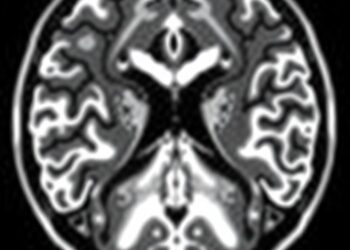

Preoperative Nigrosome Integrity Poorly Predicts DBS Results

In a groundbreaking study published in npj Parkinson’s Disease, researchers have unveiled a critical insight into the predictive value of ...